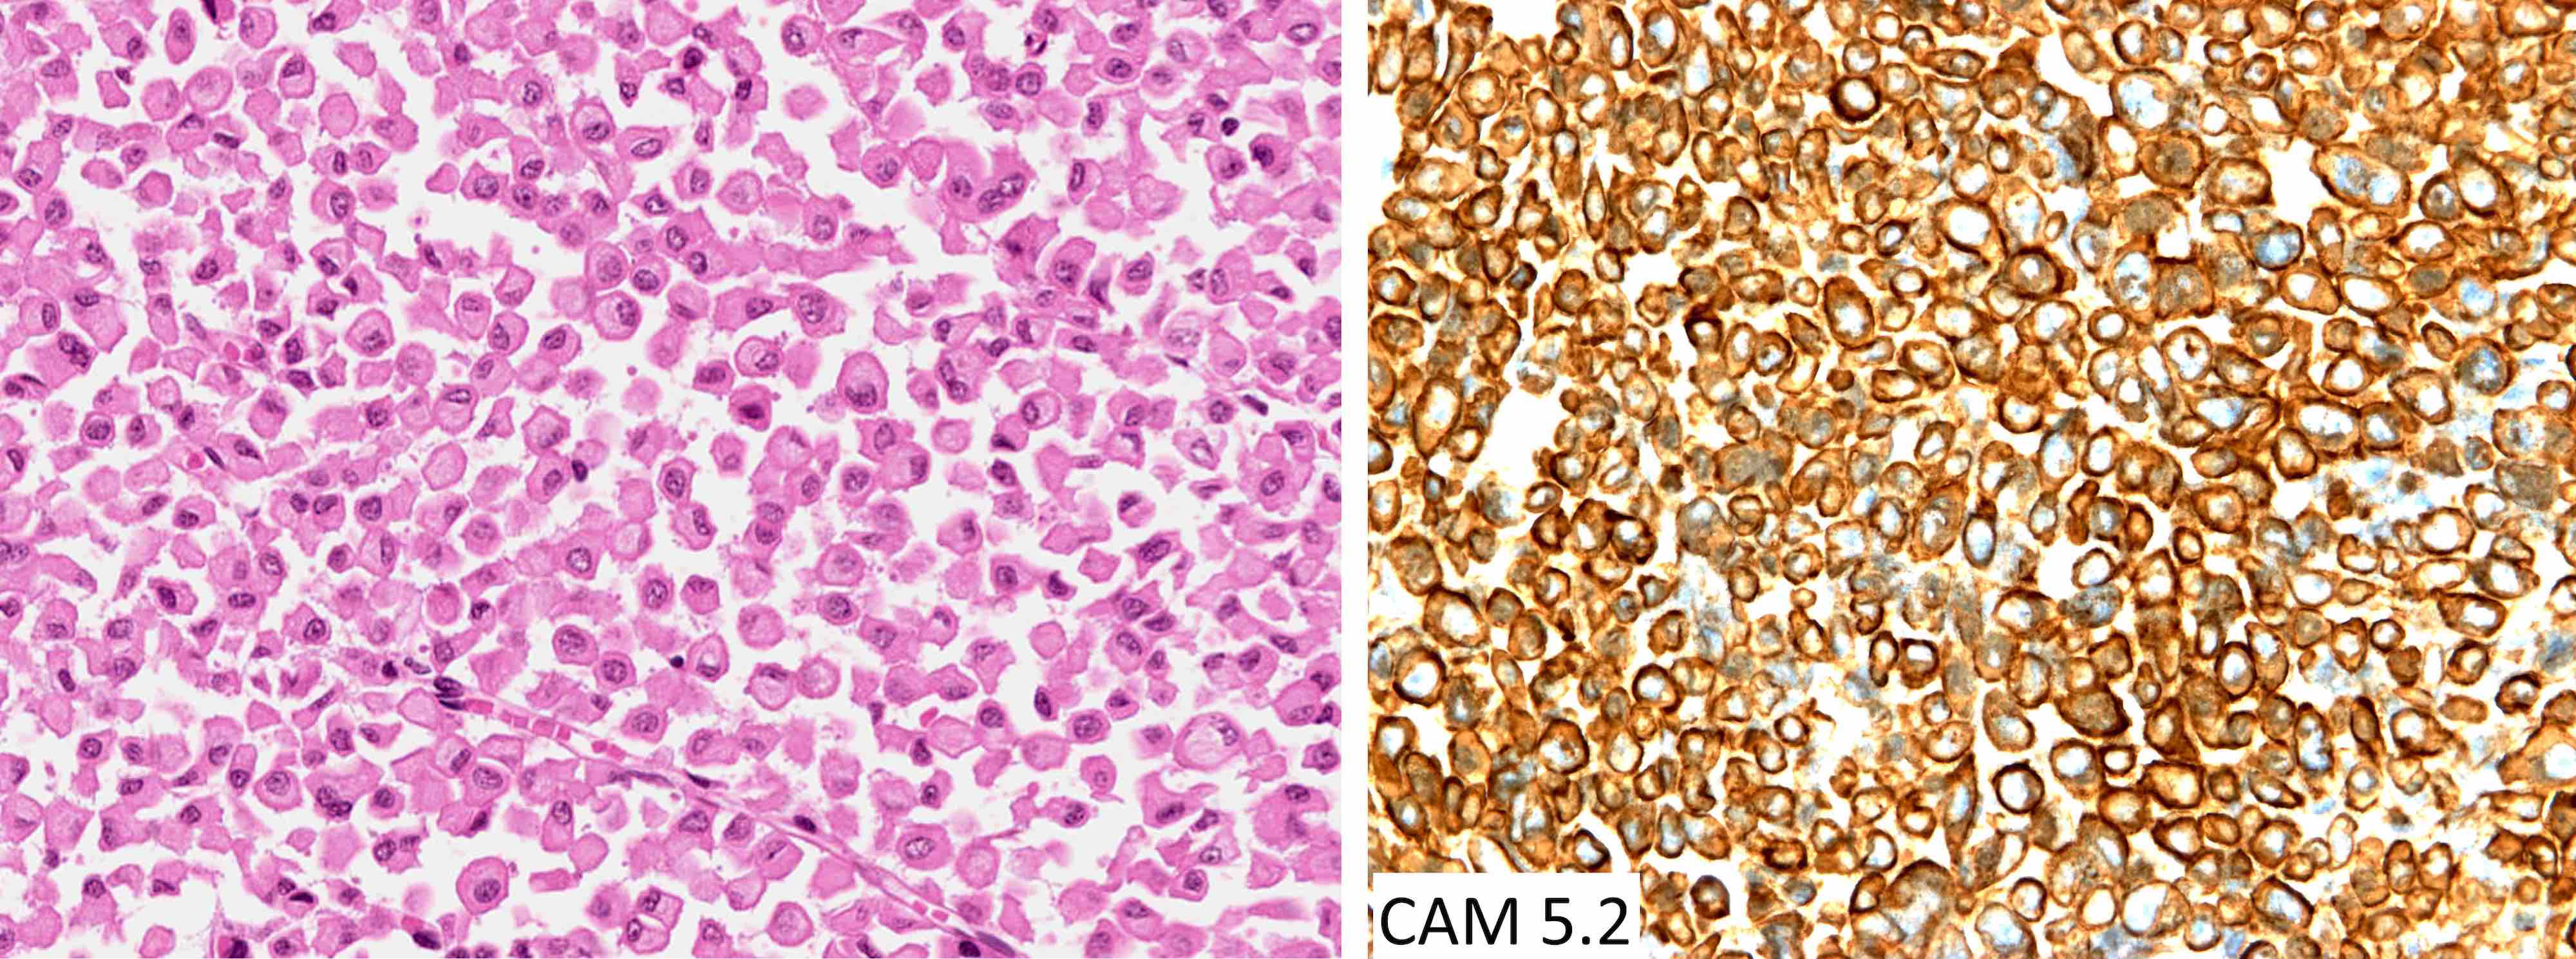

Microscopic (histologic) images

Contributed by Sylvia L. Asa, M.D., Ph.D.

Positive stains

- Paranuclear CAM 5.2 positive fibrous bodies are a conspicuous feature present in > 70% of tumor cells of sparsely granulated somatotroph tumors

The chromophobic tumor in the image above has the keratin pattern shown on the right. Which of the following is correct?

- This patient had acromegaly

- This patient had Cushing disease

- This patient would not have had hyperprolactinemia

- This tumor is likely to respond to first generation somatostatin analogues

- This tumor stains for Tpit

Practice answer #2

A. This patient had acromegaly. This sparsely granulated somatotroph tumor stains for Pit1 (not Tpit) and causes acromegaly, which may be associated with hyperprolactinemia due to the stalk section effect since sparsely granulated tumors are often large at the time of diagnosis. These tumors generally do not respond to first generation somatostatin analogues. Somatotroph tumors do not cause Cushing disease.